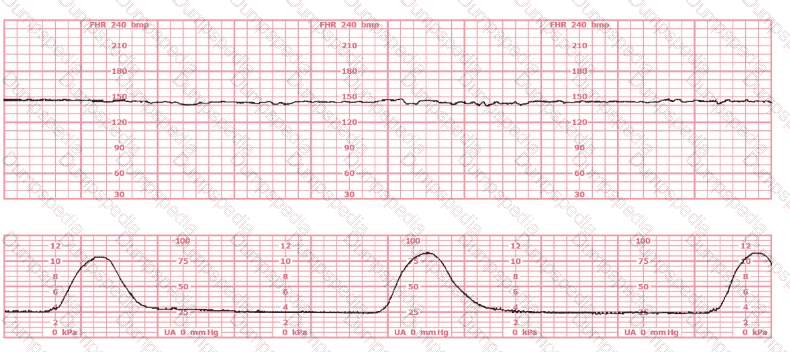

A woman at 39-weeks gestation is being induced. She has chronic hypertension controlled by methyldopa (Aldomet). Spontaneous rupture of membranes has occurred; she is 10 cm dilated and at +1 station. The fetal monitor tracing shown is obtained by spiral electrode and tocodynamometer. The next best appropriate action is to: